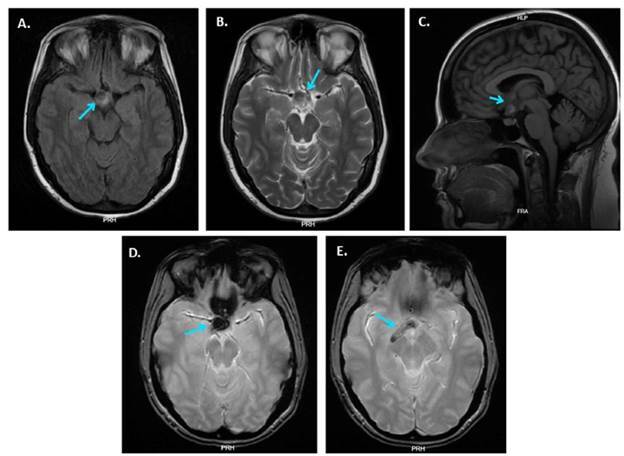

Material and methods: A 41-year-old multigravida at 23.6 weeks of gestation was admitted to a high-complexity private clinic due to significant bilateral visual acuity reduction and headache. A diagnosis of craniopharyngioma was made, and expectant management was chosen. The patient underwent an uncomplicated cesarean delivery. The literature review included case reports and series on pregnant women diagnosed with craniopharyngioma. Literature was searched on PubMed, EBSCO, and Scopus, along with references from the selected studies. A narrative summary of the findings is provided.

Results: Ten case reports were included. All patients presented with visual disturbances, and eight cases had diabetes insipidus. Magnetic resonance imaging (MRI) was used in nine cases, effectively identifying the tumor. Seven patients underwent craniotomy (four during pregnancy, two postpartum, and one post-abortion), while three had transsphenoidal surgery (two during pregnancy and one postpartum). Three cases experienced tumor recurrence, and two had incomplete resection. During the postpartum period, 9 cases had resolution of visual symptoms. In four cases, follow-up ranged from two to six years without evidence of recurrence.

Conclusions: In pregnant women with bitemporal hemianopsia, a possible suprasellar tumor should be suspected. MRI of the brain and sella turcica is the diagnostic modality of choice. Further studies are needed to document this condition in pregnancy and its obstetric management in greater detail.